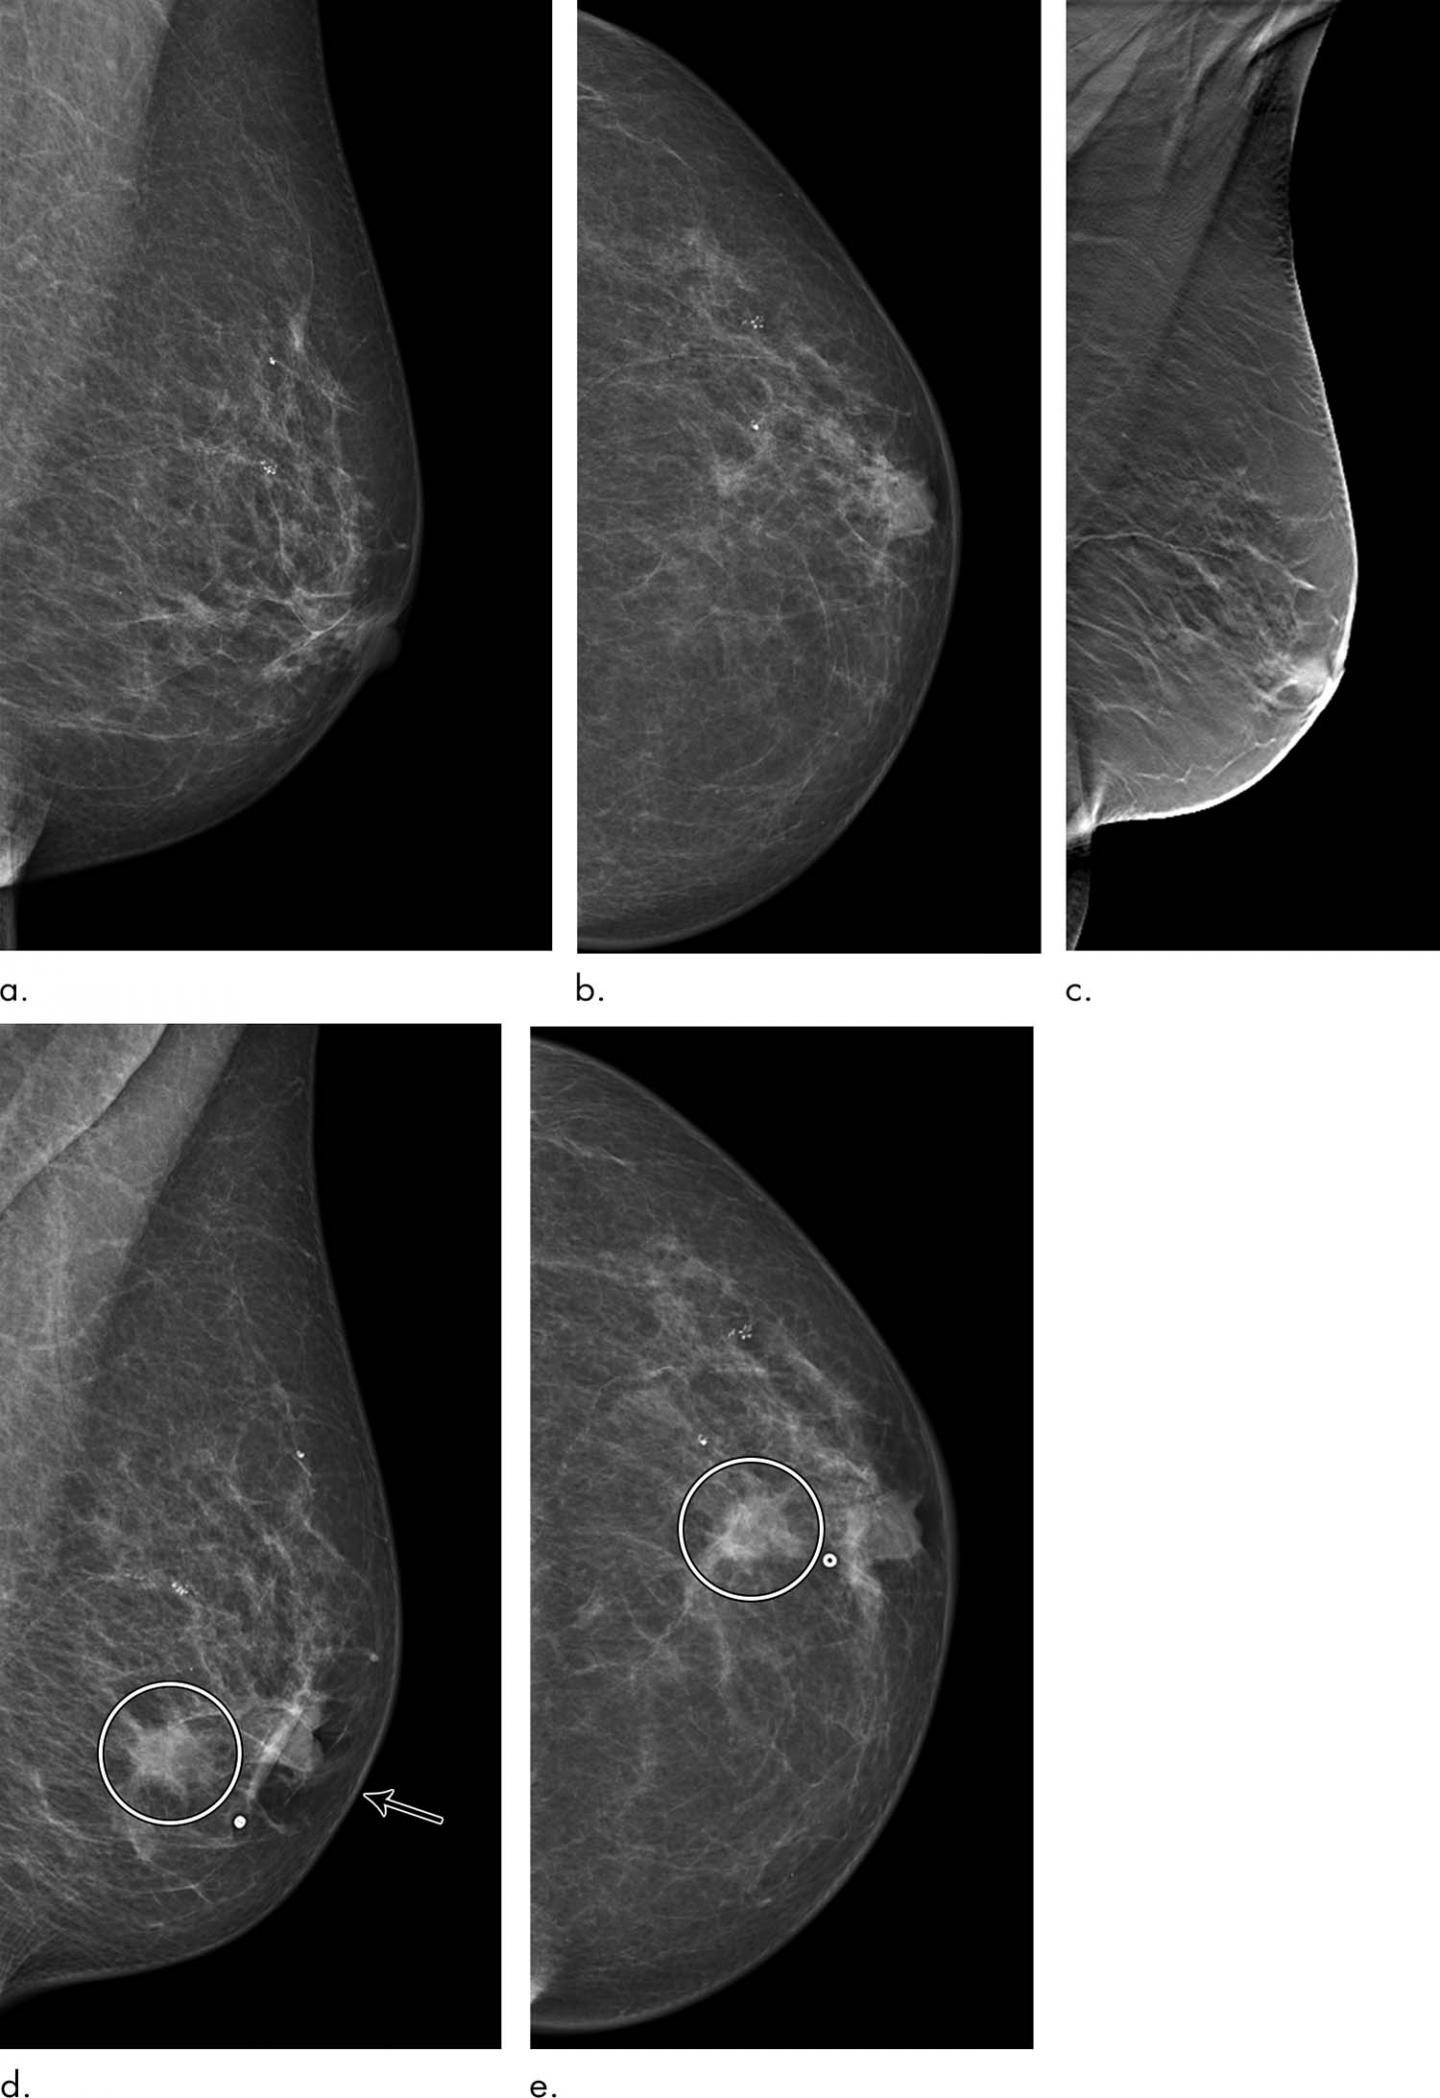

Cancers may be seen as masses (like a ball, but usually with an irregular shape), areas of asymmetry that can resemble normal tissue, calcifications (white specks), and/or areas of architectural distortion (imagine the puckering caused by pulling a thread in a piece of fabric). A tumor that is benign, it is not a health problem and it may not grow or change shape. Dr sarah jarvis mbeif a mammogram is abnormal, further tests will be needed. But radiologists can still see signs of cancer. A lump or tumor will show up as a focused white area on a mammogram.

Cancers may be seen as masses (like a ball, but usually with an irregular shape), areas of asymmetry that can resemble normal tissue, calcifications (white specks), and/or areas of architectural distortion (imagine the puckering caused by pulling a thread in a piece of fabric).

They will look carefully at the mammogram to interpret the results. How can mammograms be used? Finding breast lumps and seeing change in the size and shape. A tumor that is benign, it is not a health problem and it may not grow or change shape. A spiculated breast mass, which has spikes extending out from the main mass, is often highly suggestive of cancer.